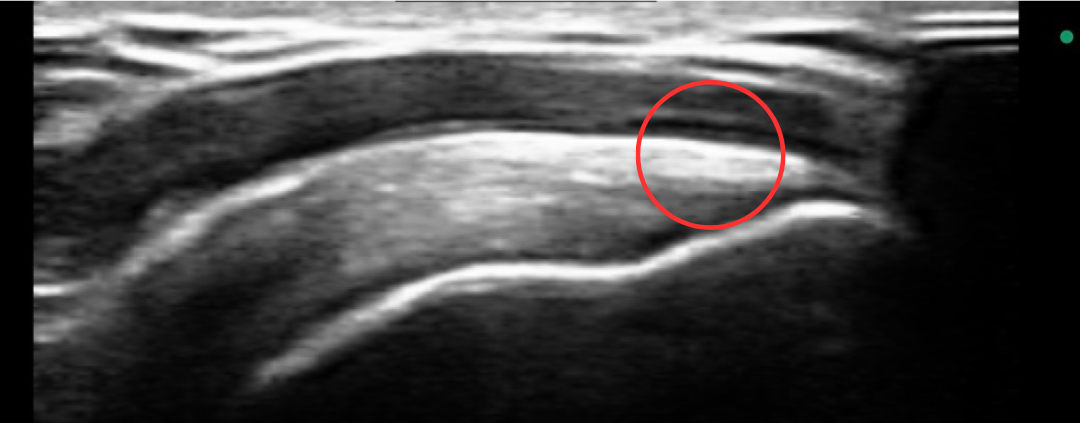

下の写真が実際に当院から精密検査を

依頼し腱板断裂と診断を受けた際の

超音波エコー検査の画像です。